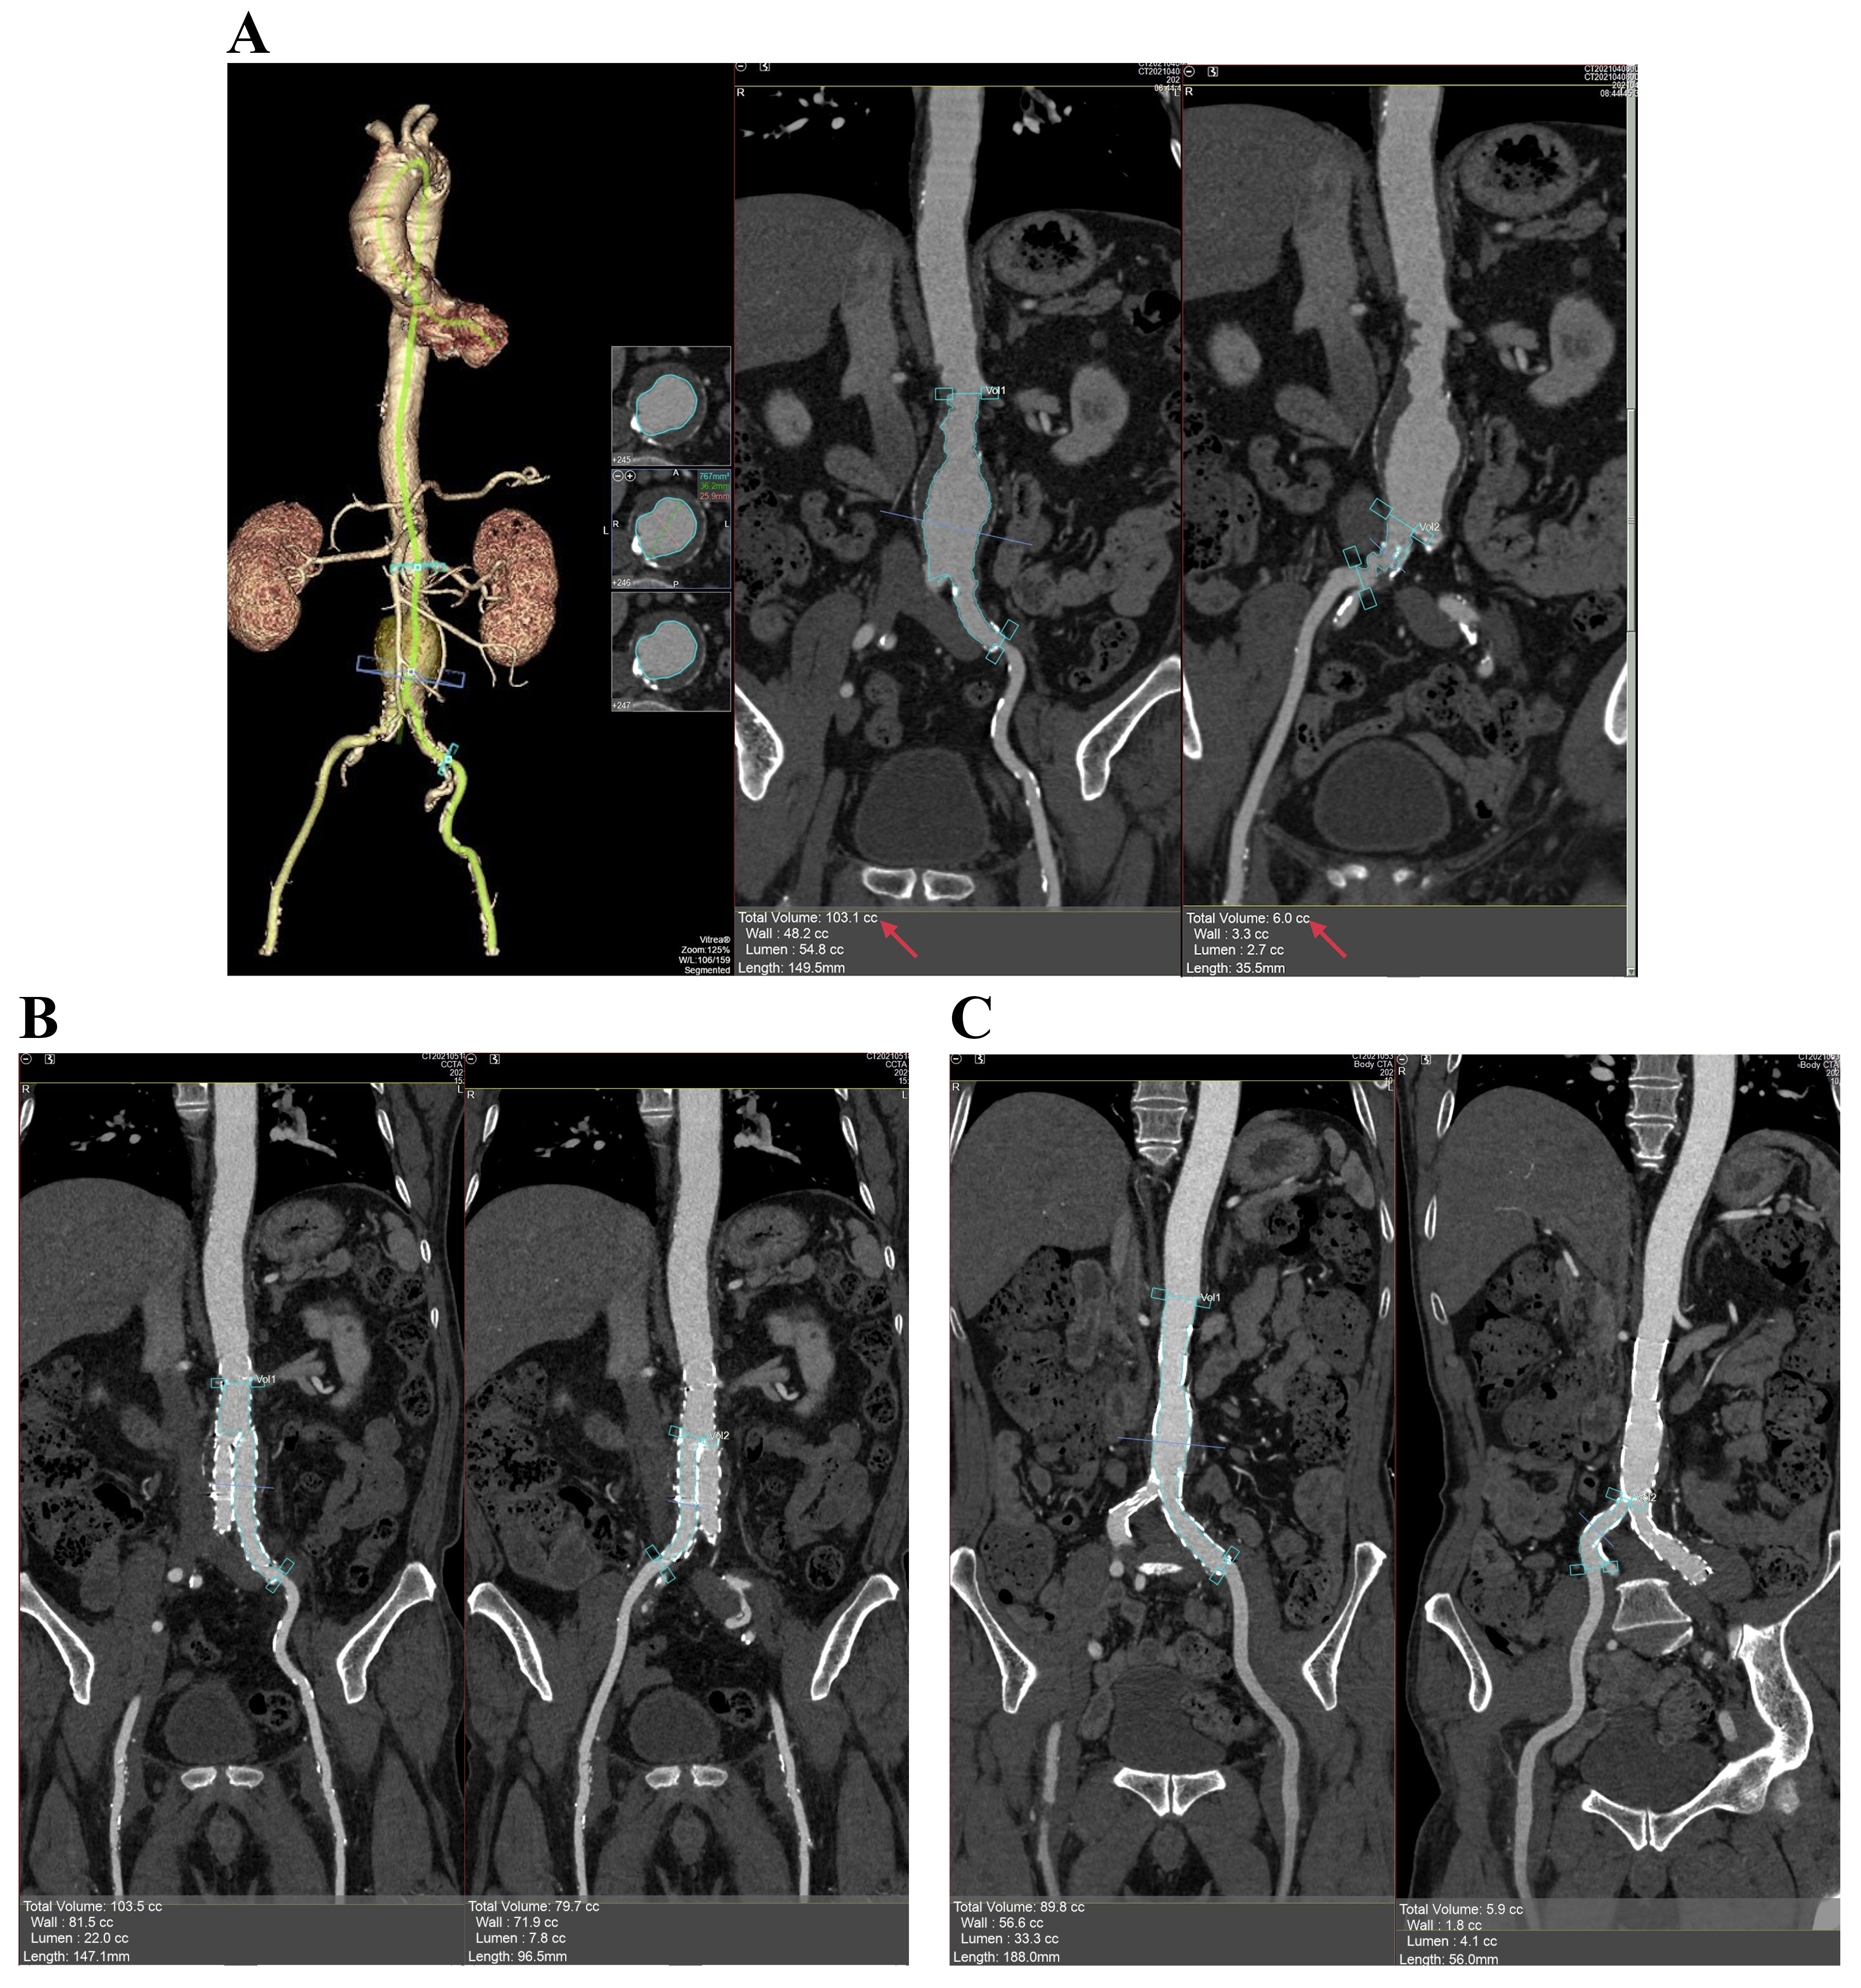

All images were analysed using a separate workstation (Vitrea FX Workstation, Vital Images, Minnetonka, MN, USA). An experienced radiologist examined the aneurysm in three-dimensional multiplanar reconstruction (MPR) and orthogonal views and then edited the centerlines of the aorta and bilateral iliac arteries in the curved MPR view to verify the accuracy. The volume tool available for vessels was used (Vascular: Aorta Stent CT protocol). The click and drag option in the curved view was used to define the proximal and distal ends (from the lowest renal artery to the end of the left common iliac artery [volume 1] and from the bifurcation of the iliac artery to the end of the right common iliac artery [volume 2]). Subsequently, the volume of the lumen (VL) was determined (except for the thrombus regions, VL = V1 + V2). The same method was used to evaluate the intrastent volume (Vs) in the same segment after the surgery (Fig. 1). Here, AAA volume loss was defined as VL – Vs.

Fig. 1.Method of volume measurement. (A) Volumes of the abdominal aortic aneurysm and bilateral iliac artery lumen before EVAR. (B,C) The volume of the intrastent (s) lumen at the level of aortic bifurcation (B) and at the level of common iliac arteries (C) after EVAR. EVAR, endovascular aneurysm repair.